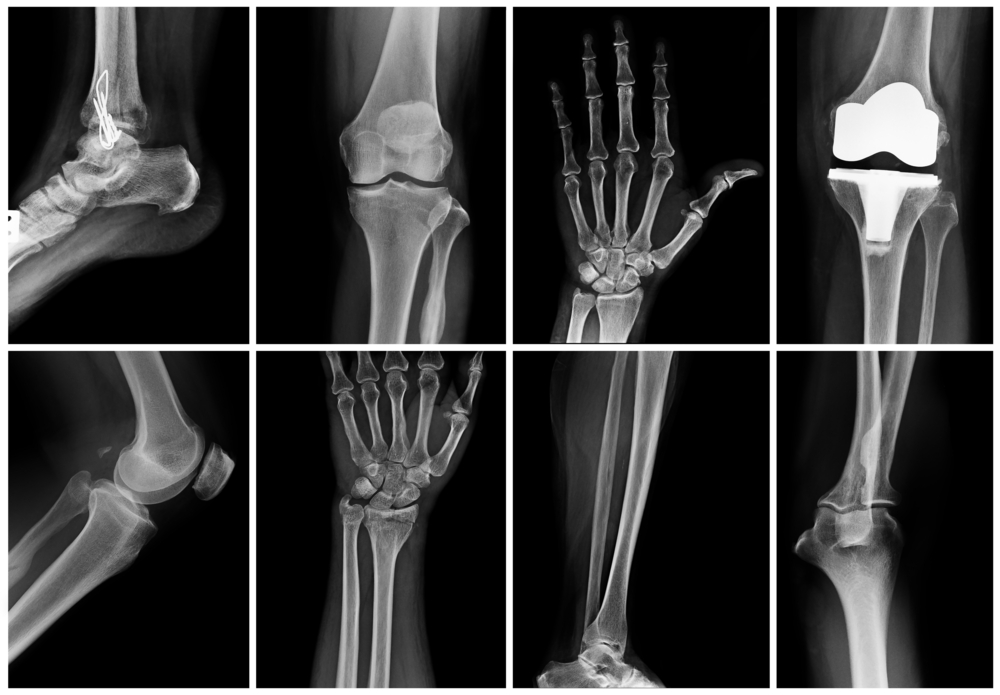

Ionizing radiation, which can damage the cells or DNA in our bodies, is all around us. Comparing that reality to a typical X-ray is useful for explaining the safety of the amount of radiation used during an X-ray.

The fact is that yes, there are more medical imaging tests run today than there were even thirty years ago, and some tests emit more radiation than others. Another fact is that the benefits from such medical tests can far outweigh any risks. Lastly, radiologists are careful to use the least amount of radiation to perform the test.

CT scans will always deliver higher doses of radiation due to the cross sectional images this particular test takes. Inversely, children being tested will have lower doses, and these comparisons will vary from above.